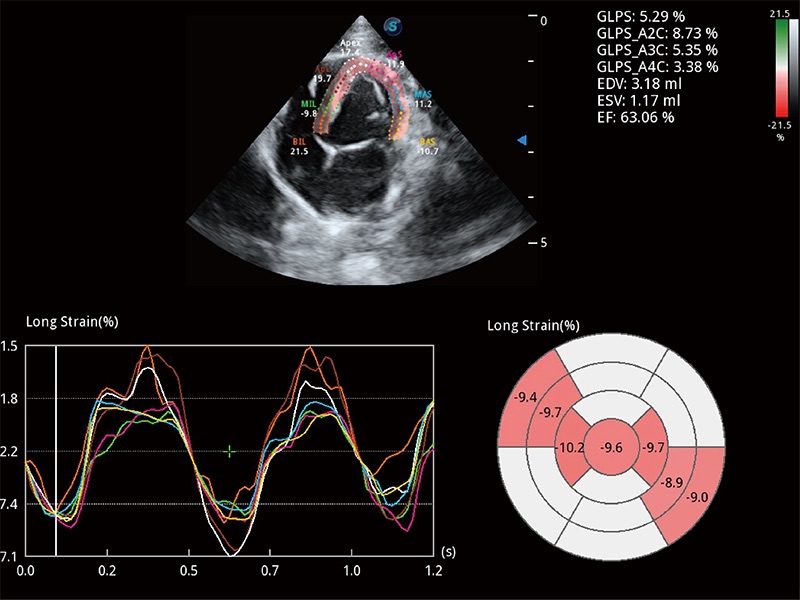

ProPet 80 配备了丰富的心脏探头群、先进的成像技术和专业的心脏测量工具,可帮助动物医生为不同体型和生理结构的动物提供心脏和心肌功能的全面评估。

实时用颜色表示心肌组织运动,观察和定量组织的运动情況,对快速检测与评估心肌的灌注和活性、电传导及心肌收缩和舒张功能等均能提供重要的诊断信息。

通过心肌识别技术与二维斑点追踪技术相结合,对心脏的超声图像进行量化分析。计算心肌17个节段的应变、应变率、速度、位移等,并通过牛眼图的形式进行呈现。

通过360度任意调节3条M型取样线,在同一心动周期上观察心脏不同位置的运动曲线,得到准确的心功能测量数据,有效评估心肌运动及左心室功能。

具备多种协议可选,同时支持17阶段划分法和专业的SE报告。

能够增加心肌组织与血流之间的区别。对于心脏扫查困难的动物,可提供更好的心内膜边界的显示。

能够基于左心室壁追踪和辛普森法,自动计算射血分数,支持多个可移动点描迹,与手动测量相比,极大节省了动物医生的时间和精力。